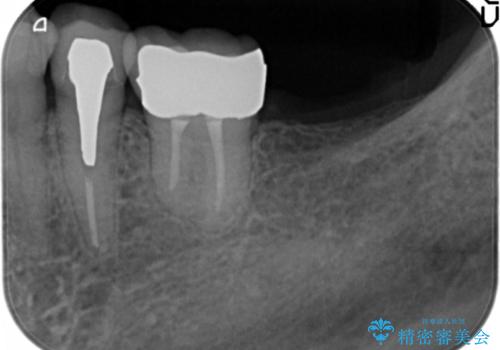

- 左下奥歯の歯ぐきから膿が出てくることを主訴に来院された患者様です。

精査したところ左下6(一番奥の歯)が破折しており、保存不可能と診断されました。

インプラント・入れ歯・自家歯牙移植(親知らずの移植)の選択肢を提案させて頂いたところ、自家歯牙移植をご希望されました。

保存不可能な奥歯(左下6)を抜歯し、機能していない親知らず(右下8)の移植を行いました。

移植後、生着を待って根管治療及び補綴修復を行いました。

左上7の挺出および対合歯の欠損を認めますが、そちらの治療はご希望されなかったため行いませんでした。